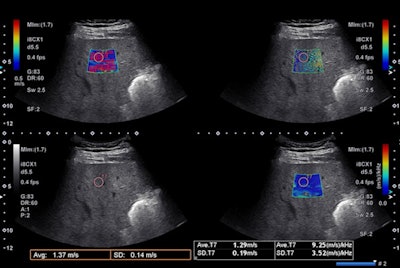

When shear waves are generated by the push-pulse of a focused ultrasound beam directly in the tissue, it's called acoustic radiation force impulse (ARFI). A convex or linear transducer transmits focused ultrasound pulses that are repeated several times in a short stint. B-mode tracking pulses detect the propagation velocity of the shear wave by measuring the difference in arrival time (time lag) between two points at known distances apart from each other, according to the article.

"ARFI-based techniques can be used for assessing the stiffness of other organs as well; however, the best application where shear-wave elastography can be considered a real breakthrough is for the noninvasive staging of liver fibrosis," Ferraioli said in an interview. "The deformation arising from tissue compression propagates laterally -- it's like when a stone is thrown in water and you see all waves. The speed of the propagation is directly related to tissue stiffness: The stiffer the tissue, the higher the speed. The speed can be converted in the measure of stiffness (kPa) using the Young's modulus and assuming that the tissue is purely elastic."

Shear-wave speed is nearly 1,000 times less than ultrasound velocity in soft tissue, with shear waves attenuating swiftly, whereas some do not propagate in simple fluids at all. Also, shear waves propagate faster in stiffer tissue than in softer tissue, a phenomenon that forms the basis for using SWE to differentiate between tissue types.

For most effective use of SWE, the ultrasound transducer should be positioned in an intercostal space -- perpendicular to the liver in both superior/inferior and right/left planes. The transducer's position can be assessed by looking at the liver capsule that appears as a sharp white line, parallel to the transducer's line, the authors said.